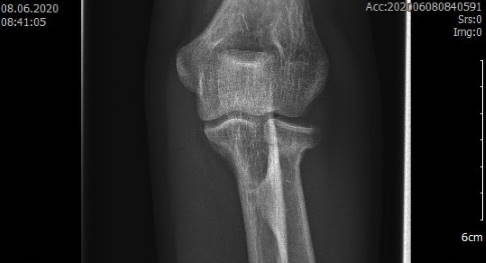

Apparative bildgebende Diagnostik: Röntgen

Die Standarduntersuchung ist die Röntgenaufnahme des Ellenbogens in zwei Ebenen. Dabei wird eine a.-p. Aufnahme angefertigt (anterior-posterior, d. h. der Strahlengang verläuft von von vorne nach hinten durch das Ellenbogengelenk). Zudem erfolgt eine seitliche Aufnahme des Ellenbogengelenks. Einfache Frakturen (Fraktur-Typ 1 und 2 nach Mason) können mit der Röntgenaufnahme sicher diagnostiziert werden.